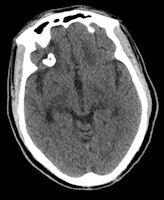

The dense calcifications seen in patients with congenital toxoplasmosis can also have a random distribution, with lesion sizes that correlate with the duration of infection. Treatment can result in shrinkage and even resolution of these calcifications (see figure).

Congenital rubella infections usually result in calcifications in the basal ganglia, periventricular regions, and brainstem, they noted. Congenital herpes infection can lead to chronic encephalitis resulting in extensive encephalomalacia and coarse calcification in the remaining brain parenchyma.

As with vascular pathologies, the mechanism of calcification involved in these infections is dystrophic calcification, according to the authors. With congenital toxoplasmosis and cytomegalovirus infections, these calcifications are usually seen in the basal ganglia and periventricular areas, whereas with herpes simplex infections, the calcifications are located in the thalamic, periventricular, and gyral regions.